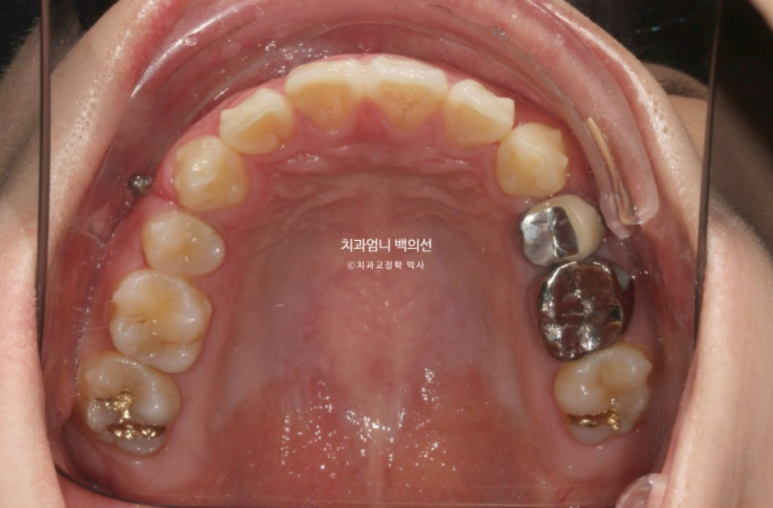

2022.12월 돌출입을 주소로 내원한 환자분 입니다.

앞니 중심선이 어긋나있고 앞니 기울어짐이 보입니다.

2022.12

앞니가 상당히 뻗쳐있는 상태 뻗침과 돌출이 심해서 입이 잘 안다물어지는 상태였고 골격분선상 골격성 2급 부정교합 (무턱)도 있습니다.

앞니가 뻗쳐있는 심한 돌출입은 당연히 발치교정을 해야합니다.

인비절라인 치료 선택하셨고 치료에 들어갔습니다.